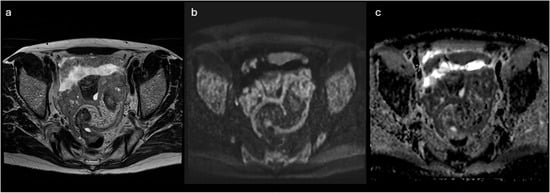

Background/Objectives: Extramedullary involvement in multiple myeloma represents an aggressive disease phenotype, associated with reduced survival and an unfavorable prognosis. Thoracic manifestations are rare and remain poorly characterized in the literature. Methods: We conducted a retrospective, single-center study at the Fundeni Clinical

Background/Objectives: Extramedullary involvement in multiple myeloma represents an aggressive disease phenotype, associated with reduced survival and an unfavorable prognosis. Thoracic manifestations are rare and remain poorly characterized in the literature. Methods: We conducted a retrospective, single-center study at the Fundeni Clinical Institute, including patients diagnosed with multiple myeloma between February 2010 and February 2025. The study cohort consisted of 34 patients with infiltration of the pulmonary parenchyma, pleura, or the presence of myelomatous pleural effusion. Diagnosis was confirmed using a combination of imaging modalities (computed tomography or magnetic resonance imaging), cytological examination, immunophenotyping, and histopathological confirmation whenever feasible. Results: Out of a total of 2012 patients with multiple myeloma, the incidence of pleuro-pulmonary extramedullary involvement was 1.6%. The median age at diagnosis was 58 years. Pleuro-pulmonary disease was present at initial diagnosis in 26.5% of cases, while 73.5% developed it at relapse. The most common presentation involved combined pleural involvement and myelomatous effusion (70.6%). Adverse prognostic markers included elevated β2-microglobulin levels (in over 80% of cases) and increased lactate dehydrogenase (LDH) in approximately 50%. Cytogenetic abnormalities such as del(17p), t(4;14), t(14;16), t(11;14), and 1q gain were identified. The median overall survival (OS) from the diagnosis of pleuro-pulmonary extramedullary disease was 16 months, with a 2-year survival rate of 25%. No patient survived beyond 5 years. The median progression-free survival (PFS) was 9 months. Conclusions: Our findings confirm the aggressive clinical course and poor prognosis of these disease manifestations, mainly when they occur at relapse. In the absence of standardized treatment guidelines, individualizing therapy and accessing novel strategies may be essential for improving patient survival.